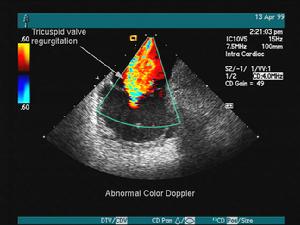

心臟彩超心臟超聲可以對心臟形態、室壁運動以及左心室功能進行檢查,是目前最常用的檢查手段之一。血管內超聲可以明確冠狀動脈內的管壁形態及狹窄程度,是一項很有前景的新技術。